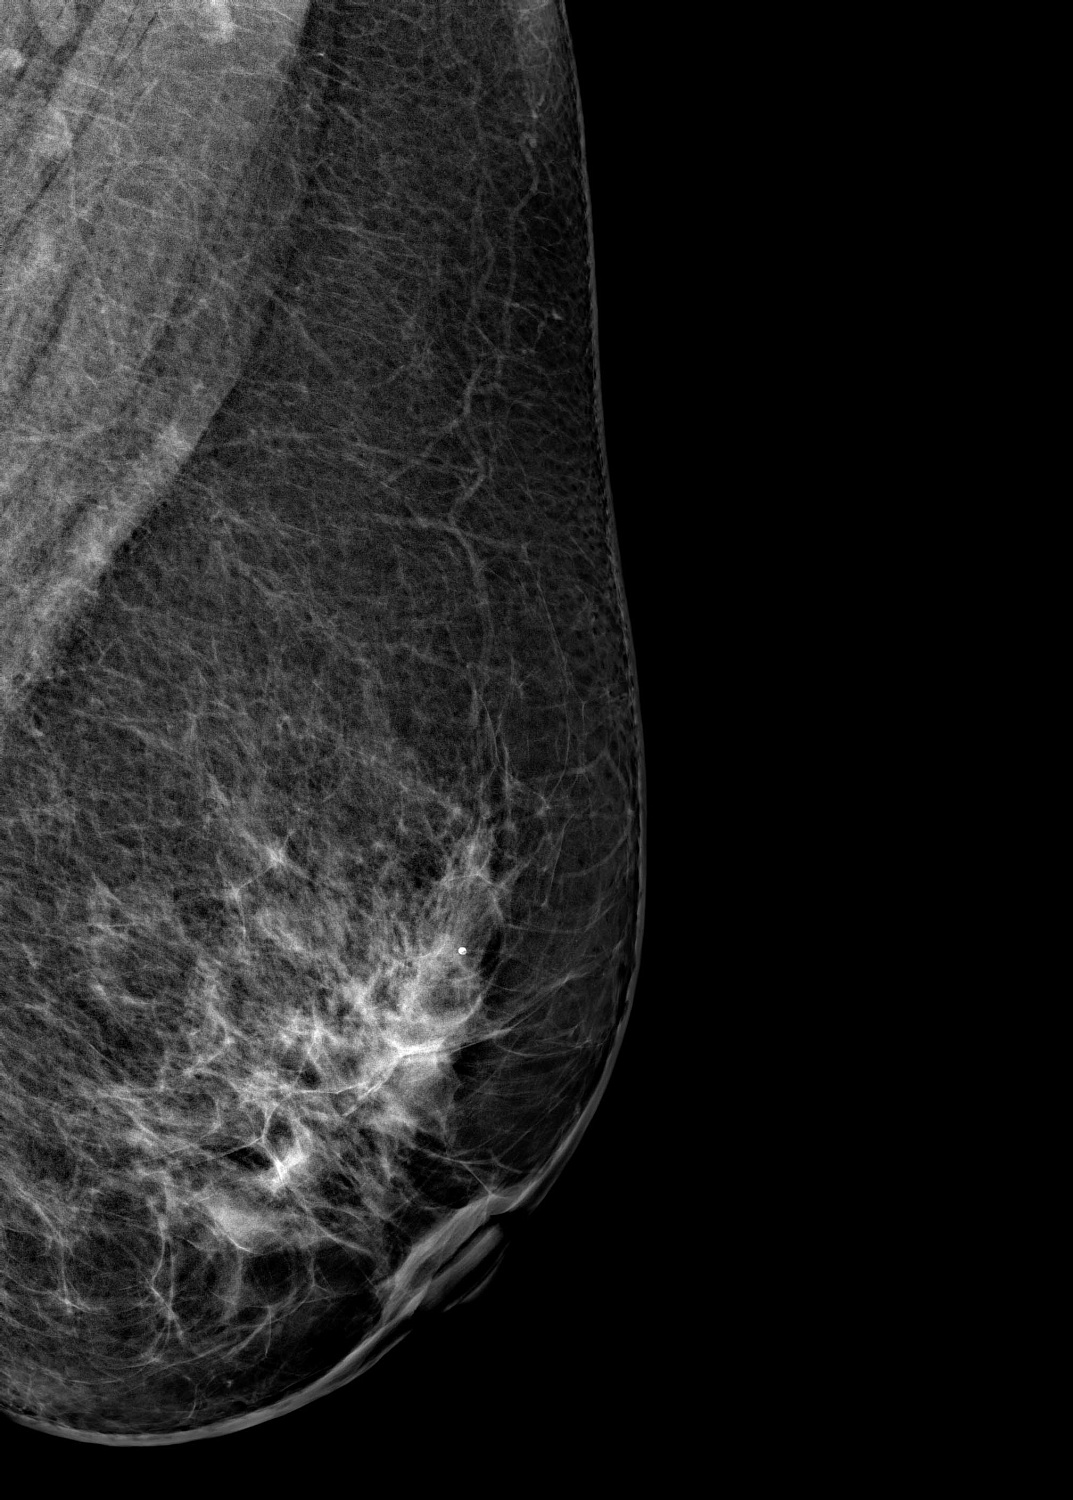

Маммограф выявляет опухоли молочной железы размером от 1-2 мм, которые не определяются при осмотре врача и самообследовании. На снимках хорошо различимы мельчайшие скопления солей кальция (от 87 мкм), тяжистые и другие перестройки тканей, характерные для рака груди 1-2 стадии. Высокую информативность, диагностическую ценность изображений обеспечивает цифровой детектор с самым чувствительным в мире сцинтиллятором. На снимках также определяются воспалительные процессы, кисты и даже небольшие повреждения.

Универсальный размер детектора делает обследование женщин с большим размером груди проще и безопаснее. Функция съемки молочных желез с имплантами позволяет обследовать эту категорию пациенток. На снимках хорошо различимы и ткани груди, и грудные эндопротезы.

Рентгеновский маммограф BRESTIGE EXPERT INDIRECT оснащен чувствительным сенсором непрямого преобразования на основе аморфного кремния. Цифровой детектор этого типа отличается надежностью и обеспечивает высокое качество изображения. Детальная «картинка» получается благодаря активной матрице, содержащей 2816 × 3584 пикселей, и хорошей квантовой эффективности (до 50%). На снимках ясно различимы даже небольшие изменения в структуре тканей и малоконтрастные образования.

Полноформатный детектор облегчает и ускоряет обследование женщин с большими молочными железами, а также делает его безопаснее. Пациенткам с грудью до пятого размера включительно для полноценного исследования достаточно 4 снимков: по 2 для каждой молочной железы. Аппараты, укомплектованные детектором меньшего размера, требуют 8 экспозиций.

Режим позволяет проводить маммографию у пациенток с грудными эндопротезами. На снимках хорошо видны ткани груди. Снимки отражают состояние импланта, в том числе его серьезные повреждения.